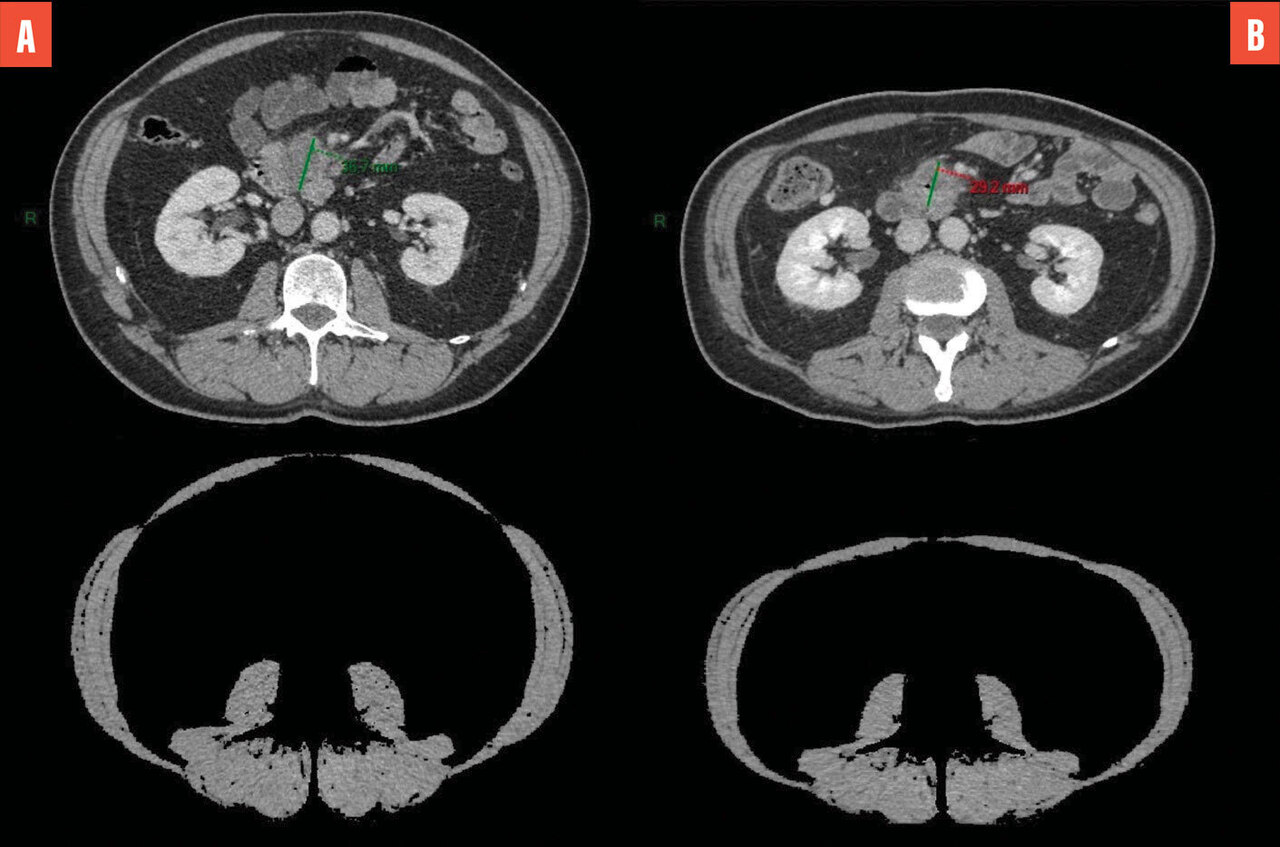

Les objectifs visés sont importants, consistant à optimiser la prédiction de la mortalité, de la morbidité, parfois l’apparition de lésions cancéreuses.2 De manière schématique, l’imagerie d’opportunité concerne principalement aujourd’hui les marqueurs de la maladie cardiovasculaire, les marqueurs d’ostéoporose et les marqueurs liés à la sarcopénie (figure). L’évaluation de la masse musculaire globale et l’identification «  opportune  » sur le scanner d’une potentielle sarcopénie permettent de prédire des évolutions péjoratives, notamment en cancérologie, indépendamment des traitements conduits.4,5 Dans une étude parue en 2023, les équipes de Pickhardt et al. ont rapporté leur expérience sur l’analyse rétrospective de 9 223 dossiers de patients ayant bénéficié d’un scanner abdominal et de l’extraction opportune de biomarqueurs quantitatifs (quantification des muscles en projection de L3, quantification de la graisse abdominale en L3 et quantification automatique du score de calcification de l’aorte abdominale).6 L’atténuation musculaire en L3 et la quantification des calcifications aortiques présentaient les meilleures performances pour prédire la survenue d’un décès dans les dix ans, avec un AUC (area under the curve ou aire sous la courbe) de 0,76 chez les hommes et de 0,72 chez les femmes, concernant l’atténuation musculaire.6